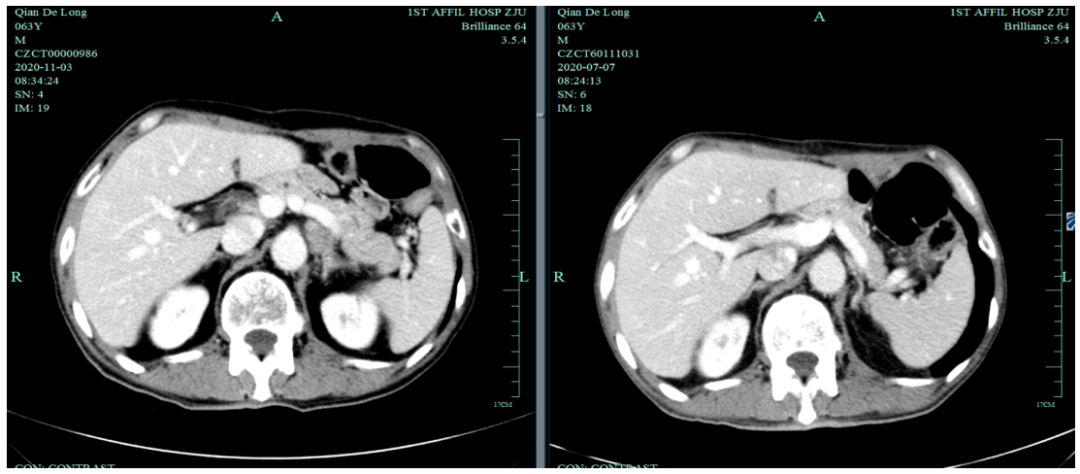

末次化疗时间为2020-7-6,定期复查于2020-11发现标记物明显升高,影像学提示疾病进展。

2020-11-3全腹部CT平扫+增强提示胃癌术后改变,术周及腹膜后多发肿大淋巴结显示,对照2020-7-7CT淋巴结肿大进展,结合临床疗效评估PD。